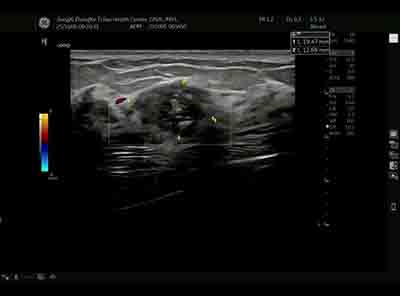

血流模式的精細評估 乳腺良惡性腫瘤的血流特征存在顯著差異。E11采用的超微細血流成像技術具有突破性意義:

可檢測流速低于1cm/s的低速血流

清晰顯示腫瘤滋養血管的走行模式

準確區分腫瘤邊緣與內部血流分布 惡性腫塊通常表現為血流豐富、走行紊亂、動靜脈瘺形成,而良性病變血流相對稀疏、走行規則。這種差異為鑒別診斷提供了重要參考。